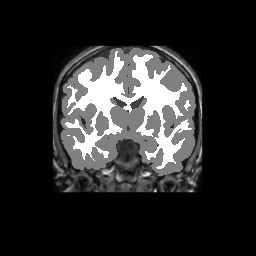

Accuracy is reported as Dice overlaps between a tool's segmentation and the Internet Brain Segmentation Repository (IBSR) manual segmentation for each of the 18 IBSR subjects. The inter-tool comparison (on the left below) shows the median Dice coefficient for each tissue class. The overlaps for FSL (from which the median values are drawn) are shown in the plot on the right.